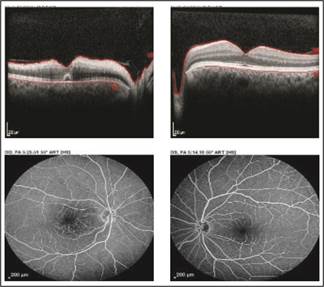

Fig. 5: IJFT type 2. Right eye showing atrophic cysts at the fovea and a gap in the IS/OS layer

Fig. 6: Cone dystrophy shows selective outer foveal degradation with loss of photoreceptors and back scattering of the light signal.

Idiopathic juxtafoveal telangiectasia can cause obscure visual symptoms. The fundus exam is initially normal. Even on FFA, early lesions are not delineated as clear telangiectatic vessels but rather as an indiscrete mild late leakage abutting the foveal area. However, on OCT the telltale sign of this disorder is a disruption of the IS/OS segment of the photoreceptor, atrophic cystoid changes at the fovea without exudation or thickening and a characteristic retinal ILM drape over the cysts.

4 cases were identified in which children were reported to have

decrease vision with an apparently normal fundus. Color vision tests were

consistently abnormal in all cases (Figure 06). A diagnosis of cone dystrophy

was made. Cone dystrophy is a hereditary disorder. Most cases are sporadic. The

most frequent established pattern is AD but AR and XL cases have also been

reported. In our set up owing to a high frequency of consanguineous marriages,

hereditary retinal dystrophies are seen with increasing prevalence than

reported internationally with crowding within the same family. These children

present with more severe forms and sometimes atypical forms of this disease. 4 major categories of

SD – OCT findings have been defined by Cho,16 based on the status

of the ellipsoid portion of the photoreceptor inner segment (ISe), outer

segment (OS) contact cylinder, and retinal pigment epithelium (RPE) layer. The more subtly presenting subtypes will

present with an essentially normal fundus and the child would be symptomatic.